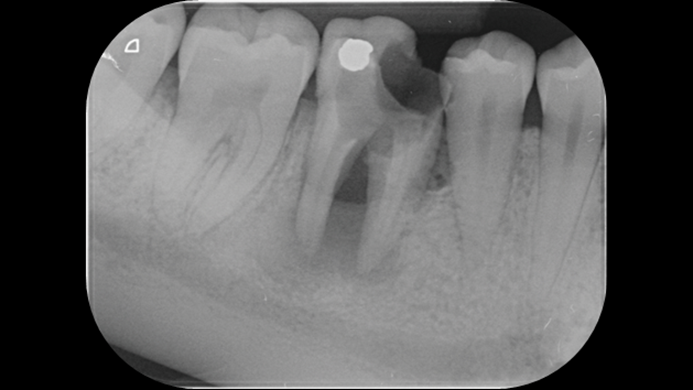

Clinical case: Installation of dental implants in complicated anatomic conditions using crest lifting methods

- Courtesy of Dr.Alexander Lysov, Russia -

AnyRidge, complicated anatomic conditions, crest lift, MICA Kit, Dr. Alexander Lysov, bone regeneration, GBR, #26, maxillary posterior